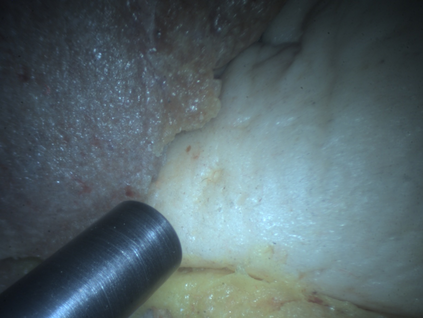

In surgical oncology, it is challenging for surgeons to identify lymph nodes and completely resect cancer even with pre-operative imaging systems like PET and CT, because of the lack of reliable intraoperative visualization tools. Endoscopic radio-guided cancer detection and resection has recently been evaluated whereby a novel tethered laparoscopic gamma detector is used to localize a preoperatively injected radiotracer. This can both enhance the endoscopic imaging and complement preoperative nuclear imaging data. However, gamma activity visualization is challenging to present to the operator because the probe is non-imaging and it does not visibly indicate the activity origination on the tissue surface. Initial failed attempts used segmentation or geometric methods, but led to the discovery that it could be resolved by leveraging high-dimensional image features and probe position information. To demonstrate the effectiveness of this solution, we designed and implemented a simple regression network that successfully addressed the problem. To further validate the proposed solution, we acquired and publicly released two datasets captured using a custom-designed, portable stereo laparoscope system. Through intensive experimentation, we demonstrated that our method can successfully and effectively detect the sensing area, establishing a new performance benchmark. Code and data are available at https://github.com/br0202/Sensing_area_detection.git